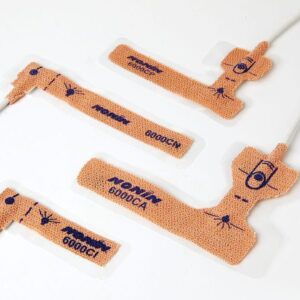

Nemi fyrir súrefnismettun – einnota fullorðins

- Available in a Variety of Sizes With sizes from neonate to adult you can ensure a proper fit for a reliable reading